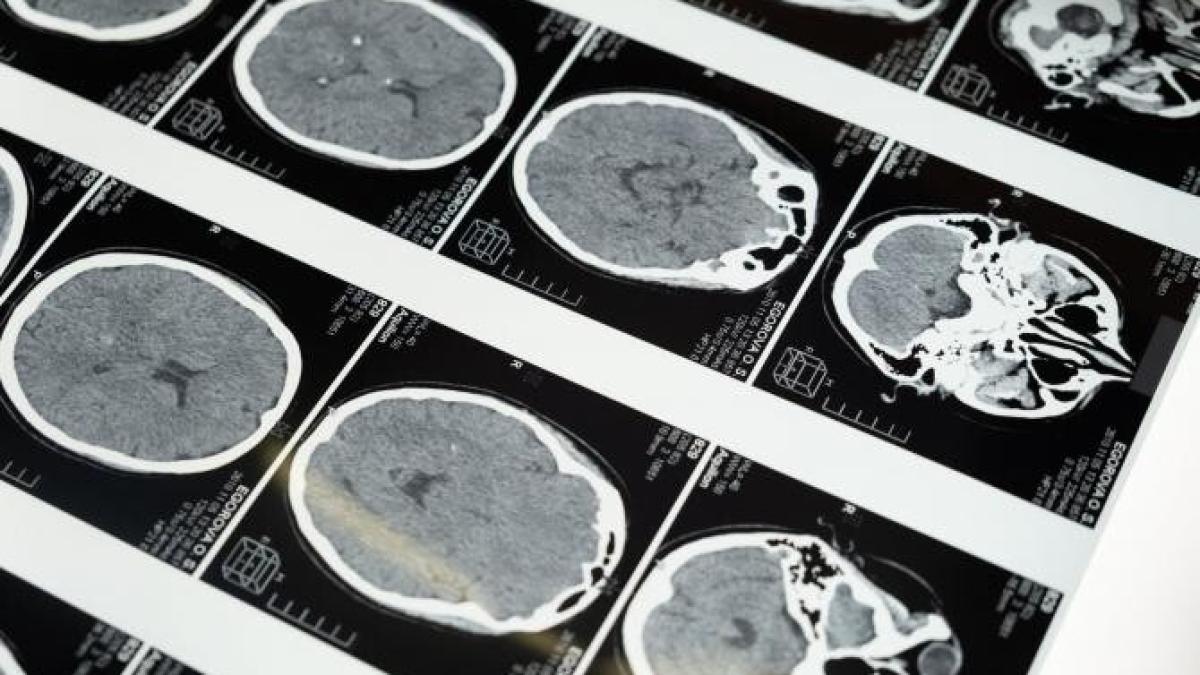

Descoperirile unui nou studiu din Statele Unite susțin ipoteza activității cerebrale post mortem.

În lumea științifică era acceptată ipoteza conform căreia celulele din creier mor odată cu încetarea activității vitale din restul corpului. Noi descoperiri contrazic acest fapt, descoperindu-se un nou tip de celule care se activează odată cu decesul și se dezvoltă, creierul uman fiind încă activ după deces, scrie RT

Medicul Jeffrey Loeb, cercetător al Universității din Illinois și conducător al studiului, spune că descoperirile sale ar putea fi o surpriză pentru lumea științifică. Este vorba despre celule gliale, celule ce au un rol inflamator în creier și curăță creierul de celule moarte în urma leziunilor sau al morții.

”Multe studii presupun că totul în creier se oprește în momentul în care inima nu mai bate, dar lucrurile nu stau chiar așa. Dovezile studiului nostru vor trebui să fie interpretate în baza altor studii făcute despre țesutul creierului uman. Încă nu au fost cuantificate aceste descoperiri până acum”, a declarat Loeb.